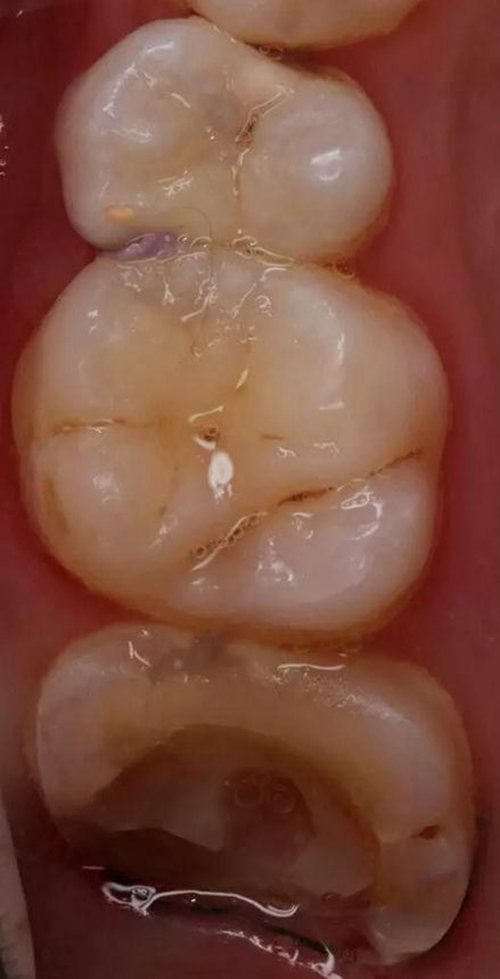

患者 女 14周歲 左上頜7牙髓炎疼痛就診

查體:27遠(yuǎn)中大面積齲壞近髓腔,探(+),冷熱(++),扣(+),無松動,口內(nèi)X片可見27遠(yuǎn)中齲壞達(dá)髓腔,牙周情況良好。

治療方案:行27根管治療,術(shù)后予以樹脂高嵌體修復(fù)。